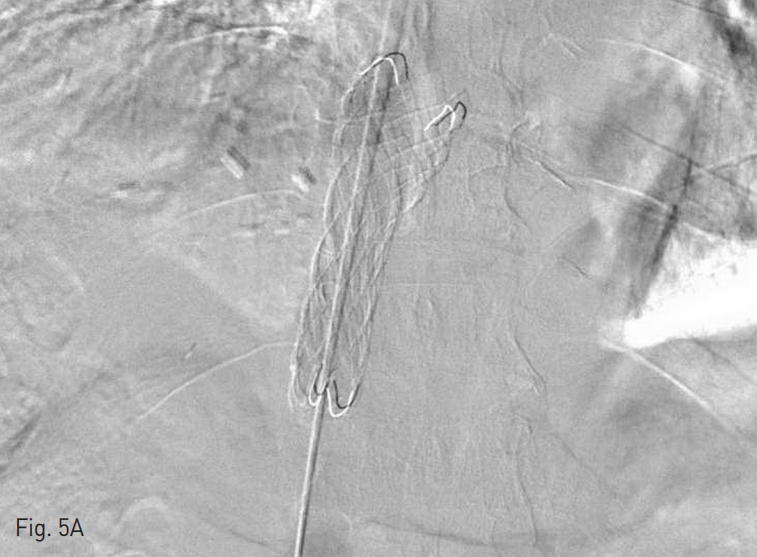

찌그러져 있던 하대정맥 이식편에는 6 mm x 4 cm balloon catheter (Mustang, Boston Scientific, Natick, MA, USA)를 사용하여 확장시켰고, 22 mm x 6 cm stent graft (S&G, Sung-nam, Korea)를 위치시킨 후 14 mm x 4 cm balloon (Mustang, Boston Scientific, Natick, MA, USA)으로 최대한 확장시켰다. 마지막으로 시행한 정맥조영술에서 혈류가 개선되었으며, 측부 순환들도 보이지 않았다 (Fig. 5).

Fig. 5

A. 22 mm x 6 cm stent was inserted in IVC graft.

B. Follow up venography shows improved blood flow and disappeared collateral circulations.